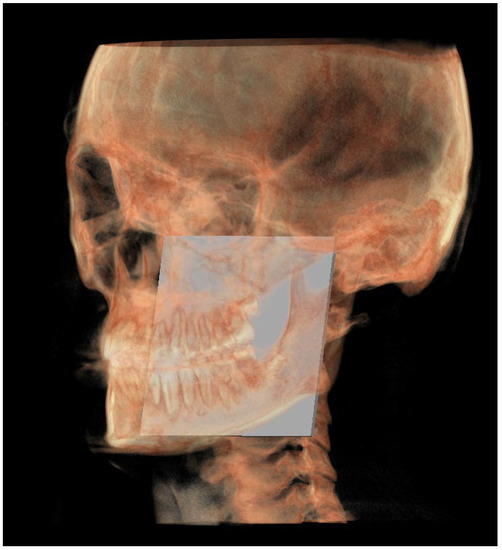

| Neutral right gonion (rGon) | Point located at the same level of the Go and halfway between the PMn line and the CPCo plane. Right side | / | / |

| Neutral left gonion (lGon) | Point located at the same level of the Go and halfway between the PMn line and the CPCo plane. Left side | / | / |

| MR neutral (MRn) | Plane passing through the mCo, rGon and lGon |

| Construction plane through Co (CPCo) | Construction plane passing through the mCo and parallel to the PMn |

| GoP | Gonion plane: plane passing through rGo and lGo normal to PMn |